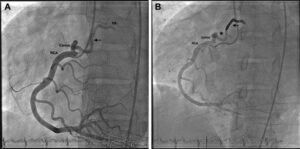

Endovascular coiling is a modern, minimally invasive procedure used to treat brain aneurysms. The procedure involves inserting a catheter through a small incision in the groin, which is then guided to the site of the aneurysm in the brain. Once in position, small coils are deployed into the aneurysm to block blood flow, thereby preventing the aneurysm from rupturing.

The endovascular coiling procedure is typically performed under general anaesthesia. During the procedure, a catheter is inserted through an artery in the groin and guided to the brain. Using imaging technology, the surgeon positions the catheter at the aneurysm site and deploys the coils to fill the aneurysm and prevent blood flow.